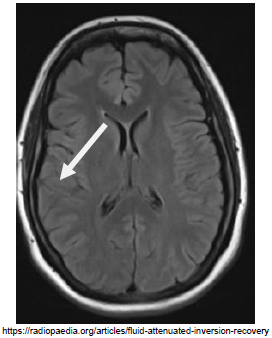

Sobre a imagem de ressonância magnética apresentada abaixo, assinale a afirmativa correta:

Observe a imagem abaixo.

A atrofia da região assinalada na imagem acima, é encontrada em qual tipo de demência?